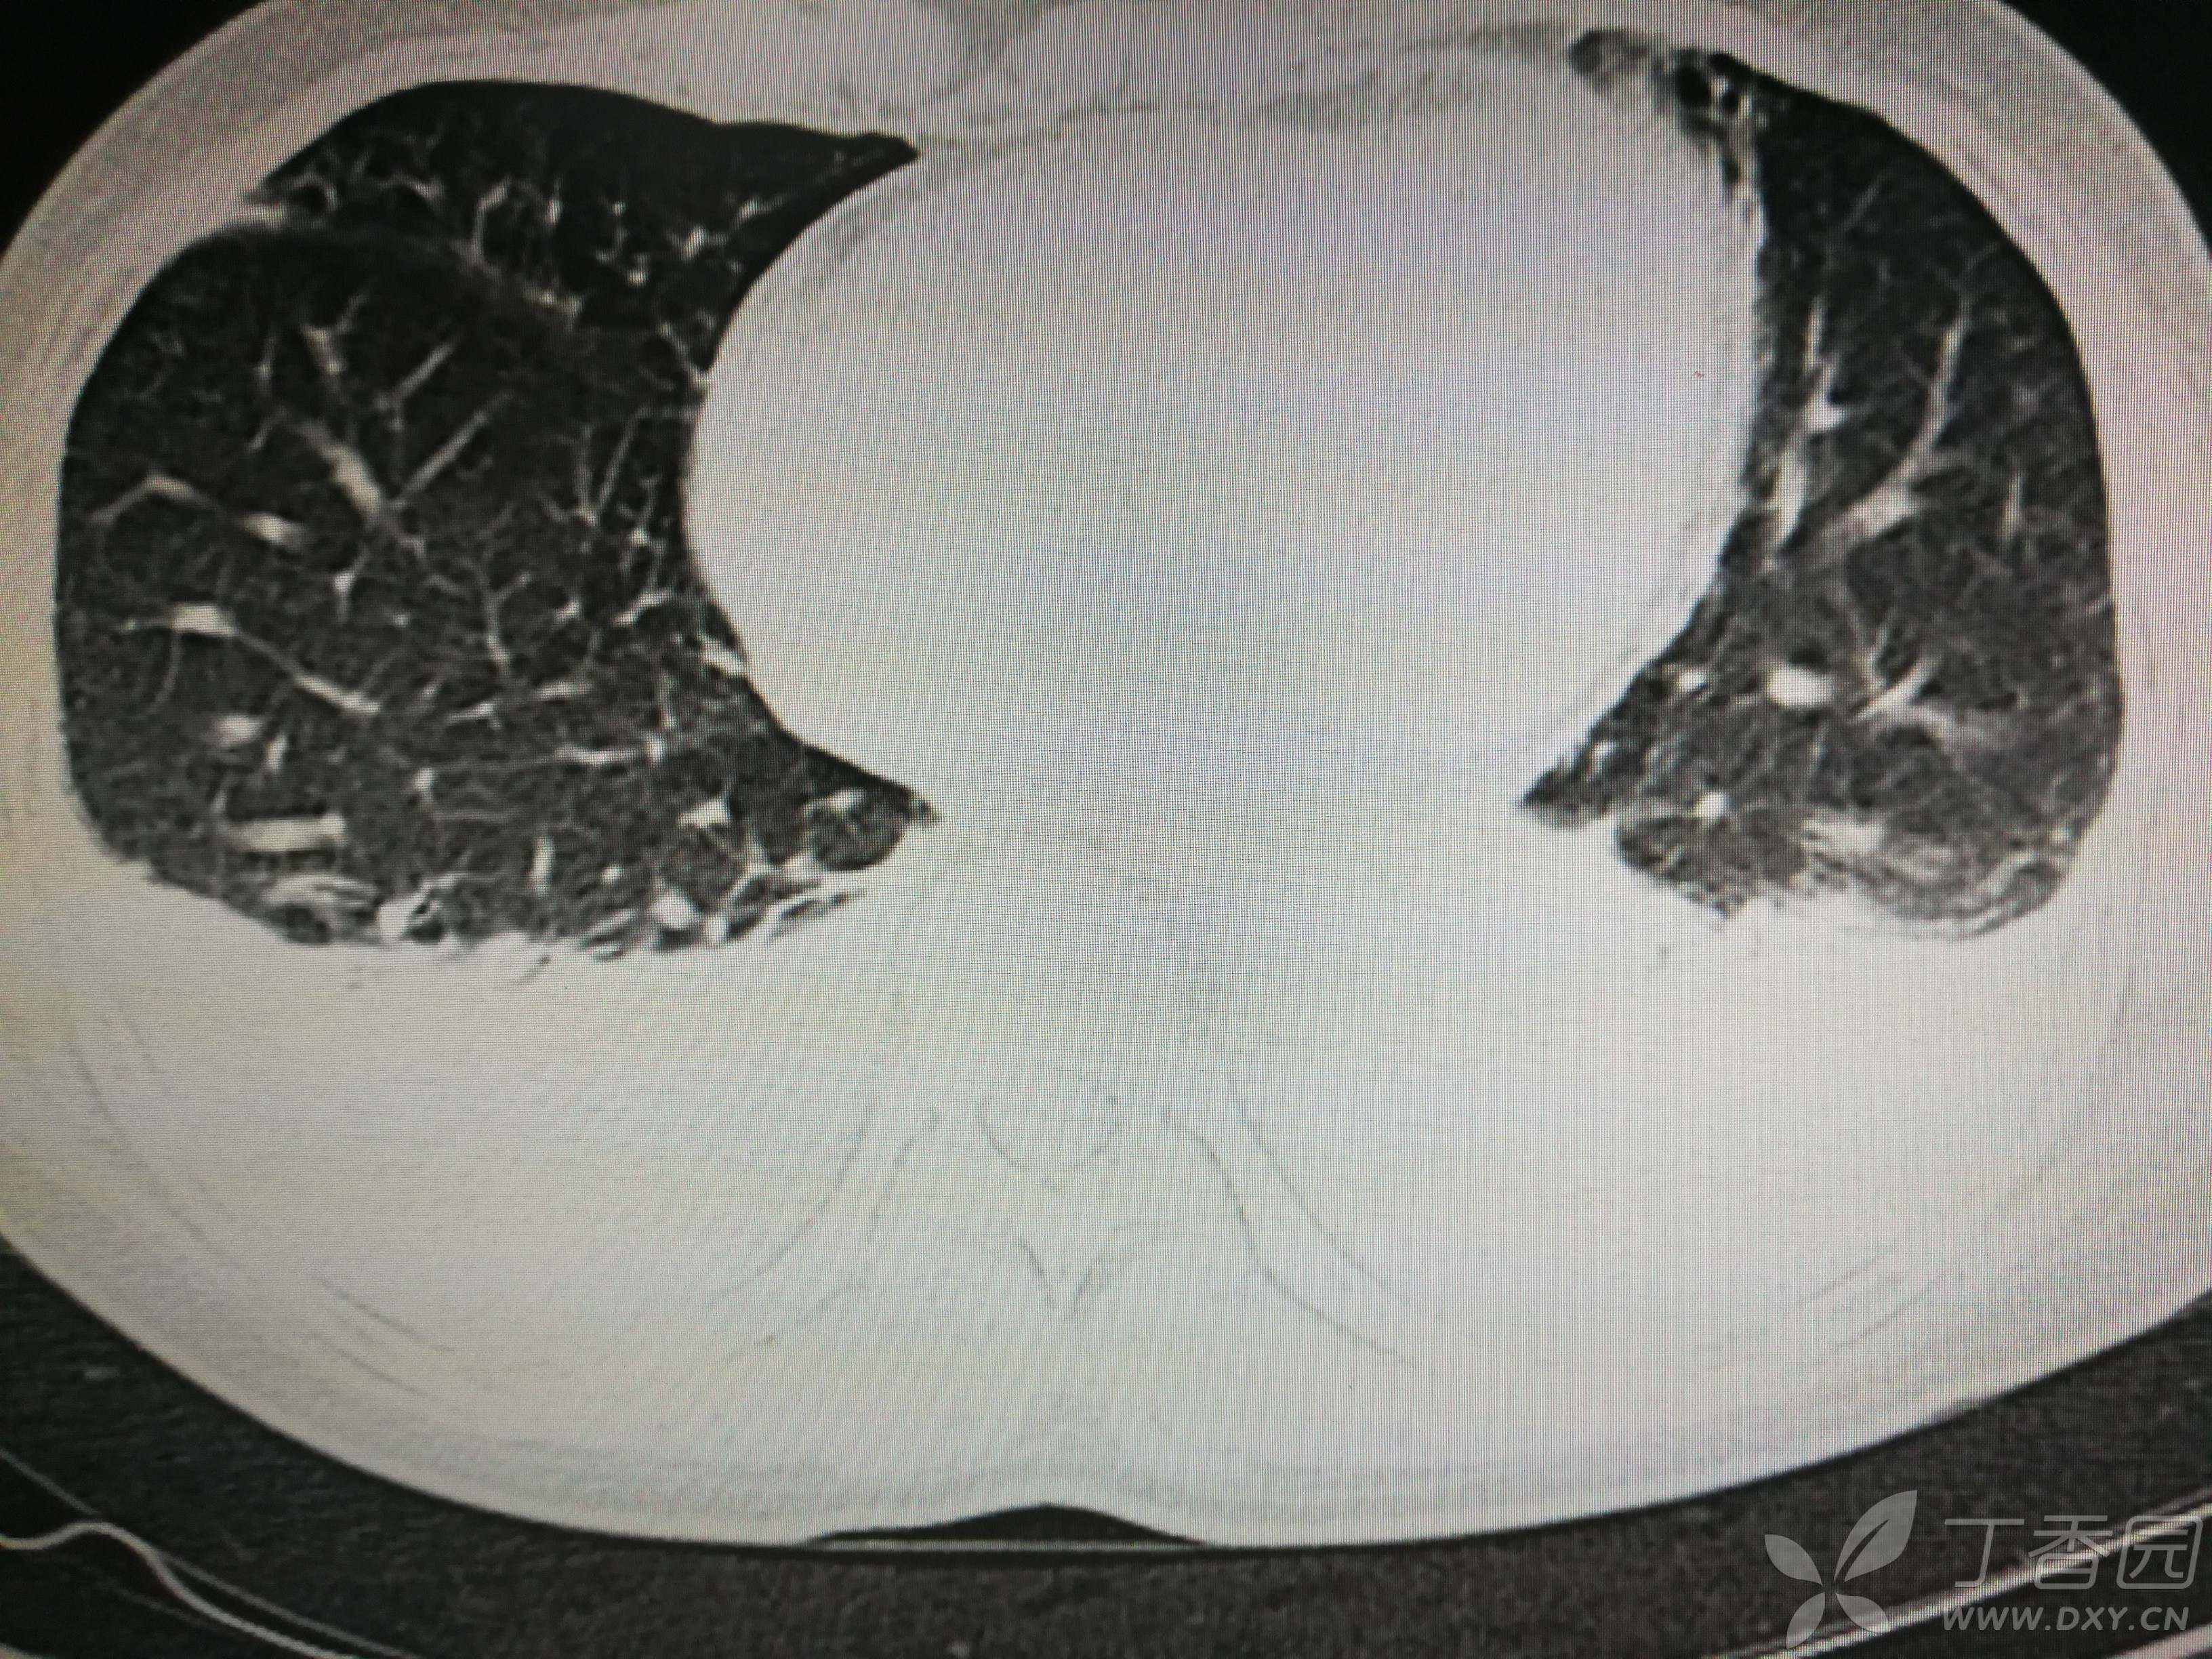

给予低分子肝素钙针抗凝、七叶皂苷钠针消肿及骨牵引固定等等治疗。入院后第四天行“左侧股骨下段骨折切开复位内固定术”(术前查双下肢彩超:双下肢深静脉血流通畅),手术顺利,术后予预防感染、预防血栓形成等治疗。术后患者无明显发热,生命体征平稳。术后第四天复查血常规:白细胞13.4×109/L,血红蛋白84g/L,血小板在正常范围。生化:白蛋白35.7g/L,余无明显异常。当天,患者开始出现轻度胸闷气急,可耐受。术后第五天患者胸闷气急加重,无胸痛,无背痛,无咯血,无意识障碍,无头晕头痛,无恶心呕吐等,急查凝血功能:纤维蛋白原降解产物12mg/L,D二聚体4000ug/L,余无明显异常。查动脉血气分析:pH7.52,氧分压62mmHg,二氧化碳分压30mmHg,碱剩余1.8mmol/L,乳酸1.0mm/L,血红蛋白86g/L。查胸部CT见下(先视频后图片):